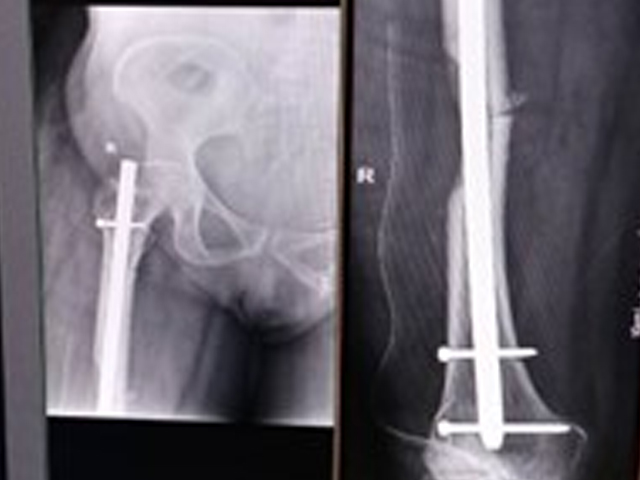

Operation Theatre

Spacious operation theatres with modern fracture table and accessory attachments. C-Arm State of the staler Arthroscopy set.

The department operates a dedicated Level-I trauma center to manage accidents and emergencies. This facility provides prompt and effective treatment for patients with polytrauma, fractures, dislocations, and other musculoskeletal injuries. The trauma center is supported by an efficient Intensive Care Unit (ICU), anaesthetists, and Trauma Surgeons We also serve as a referral center for managing complications following trauma, such as infections, non-unions, and deformities.

1 JAMP EFFECTIVESS OF MINI HACKSAW BLADE ON HANDLE FOR REMOVING BENT INTRAMEDULLARY NAILS: A CASE SERIES